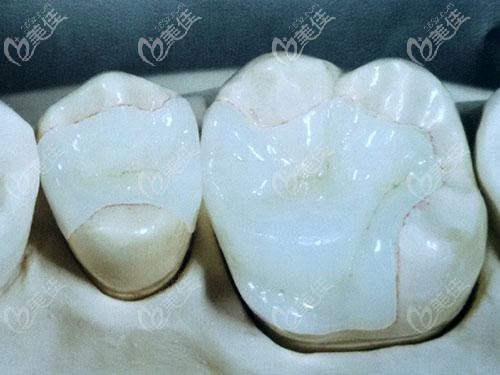

輕微齲齒補牙選擇美國3m和日本松風哪個好? b10935 G0 V0

牙齒蛀了個洞是否需要補牙要看情況,淺齲和中齲 “補牙”即可,深齲才需要做根管治療,那么輕微齲齒補牙選擇哪種材料好呢?